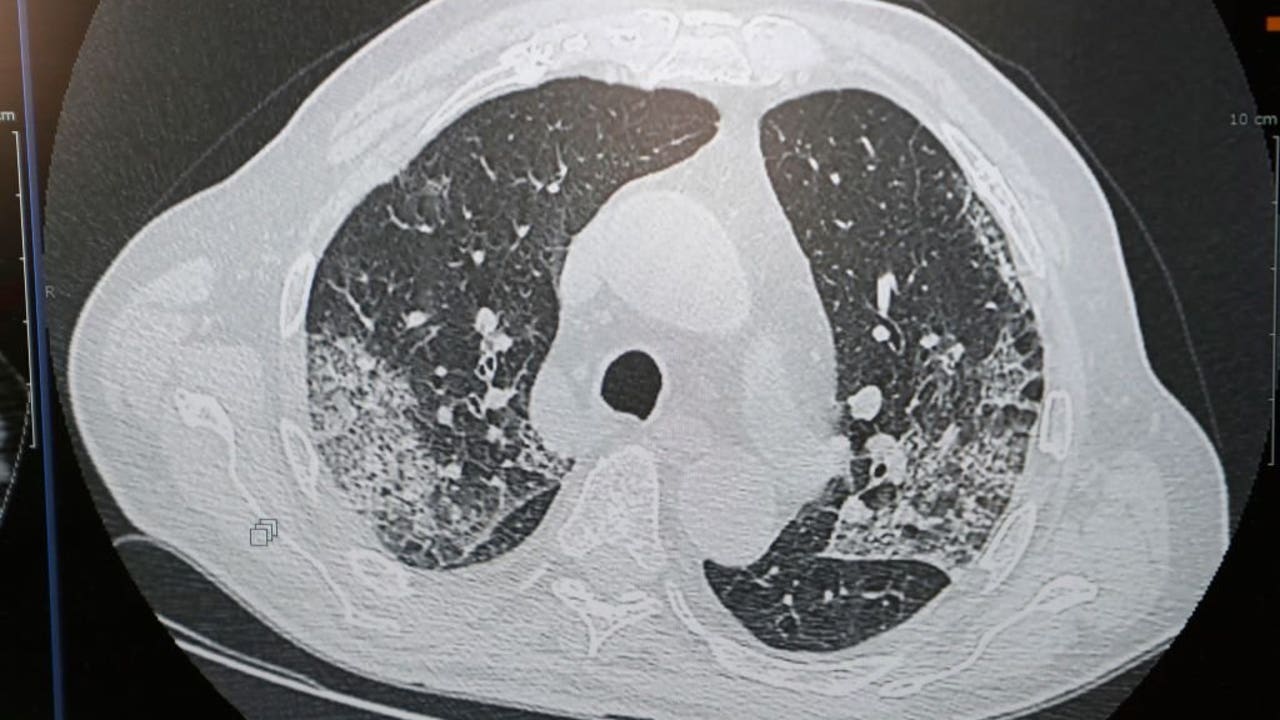

George Washington University Hospital in Washington D.C. released a 3D image of the lungs of a man who passed away from COVID-19. You can see in the yellow areas where the inflammatory cells replicate and cover much of the lungs.

Hawkinson said this coating on the inside of your lung makes it difficult for patients to breathe.

"That inflammation that includes cells, but also chemicals, really creates that layer where it is difficult for the gas exchange," Hawkinson said. "It’s difficult for you to get the oxygen you breathe into the blood system so that it can get to the rest of your body."